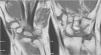

Para poder realizar la osteotomía se realizó una disección capsular del segmento más distal del mismo, adyacente al ganchoso. El HG se expone perfectamente con ayuda de 3 separadores tipo Hoffman, que se mantienen delicadamente en las interlíneas articulares proximal y laterales al HG. Se realizó una osteotomía transversal oblicua, de dorsal a palmar y de proximal a distal, justo a nivel de la parte distal de la superficie articular proximal. Esta oblicuidad se realizaba para que el posterior material de síntesis fuese perpendicular al trazo de osteotomía y ejerciese un efecto de compresión del foco. El primer corte debía ser parcial y justo proximal a este, se realizaba otro corte paralelo, preservándose siempre la cápsula volar. El acortamiento usual era de 3mm de espesor (poco más que la anchura de la sierra). La cabeza del HG grande era un fragmento muy móvil. Por ello la osteotomía proximal se realizaba primero. Una vez realizada esta, la cabeza móvil se podía comprimir contra la parte distal del HG, usando el separador de Hoffman introducido en el espacio HG-Se, sin dañar el cartílago articular. En este momento, se pasaban una o 2 agujas de Kirschner paralelas de distal a proximal, a través de la osteotomía. A través de estas agujas se llevaba a cabo un brocado con el material apropiado canulado y finalmente se colocaban uno o 2 tornillos sin cabeza que aportan compresión al foco (fig. 3). En todo momento se realizaban controles sistemáticos radiológicos peroperatorios mediante fluoroscopia, para comprobar la correcta colocación del material de síntesis.

No se apreciaron modificaciones en el índice de Youm después de la cirugía, obteniéndose un valor medio de 0,47mm. Cuatro semilunares presentaban un tipo ii (fig. 1) y 2 un tipo iii según la clasificación morfológica de Antuña Zapico. Tampoco hubo cambios significativos en las mediciones radiológicas del semilunar antes y después de la cirugía. En todos los pacientes se consiguió la consolidación del foco de la osteotomía a los 3,5 meses de media (3-5 meses) y en ningún caso se constató una necrosis del polo proximal del HG.

No existieron complicaciones de partes blandas ni ningún caso de seudoartrosis en el foco de osteotomía u osteonecrosis proximal del HG (fig. 6). No se evidenciaron complicaciones intercarpianas ni de síndrome doloroso regional complejo tras la cirugía. En un caso se necesitó la retirada del material de osteosíntesis por molestias locales con la entrada del tornillo.